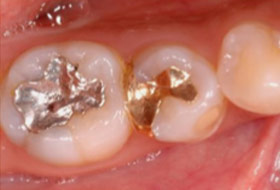

虫歯治療後には「銀色」の詰め物・被せ物を装着されると多くの方が思っていると思います。当院では患者さんの「健康」、そして「口元の美」を考慮し、可能な限り銀歯を使わず、白い詰め物などで対応しています(メタルフリー治療)。

皆さんはあまり認識されていないかもしれませんが、銀歯を付けていると金属イオンが流出し、「体の健康を害する」ことがあります。例えば、「皮膚のかゆみ・かぶれ」「アレルギー性皮膚炎」「じんましん」「頭痛」「肩こり」などなど。

その他、「色が目立つ」こともそうですが、「歯茎に金属イオンが沈着」することで、見た目が悪くなってしまう事もあります。

以上の理由から、欧米などの先進国では金属の詰め物・被せ物は使わなくなってきています。

このようにならないための素材はたくさんあります。

当院では患者さんのお口の状態、お好みなどをお伺いし、適切な素材をご提案させていただいています。